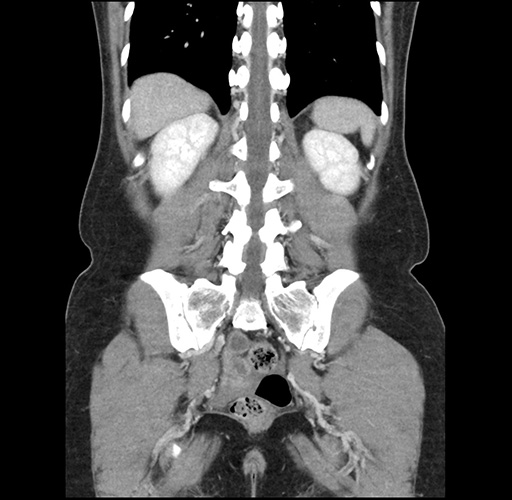

Imaging Analysis

Look through the patient's CT scan to identify any areas of concern for the necessary procedure.

Based on your CT findings, which issue(s) would give reason for "planned slowing down moment(s)" in this case?

Considering a standard left lateral sectionectomy procedure, what step(s) of the operation would you do differently in this case ?